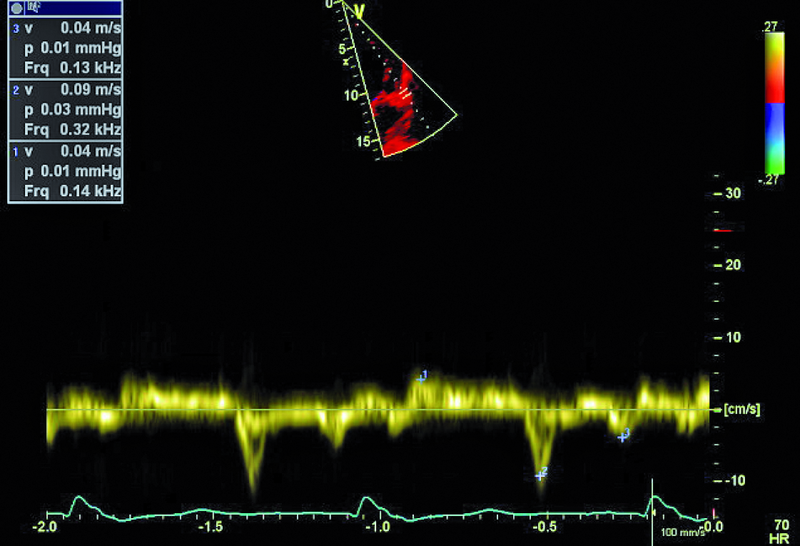

Kobieta, lat 41. Jakie patologie można rozpoznać na zamieszczonych rycinach?

4. Ciężka dysfunkcja skurczowa lewej komory (ryc. 3-5).

5. Niedomykalność zastawki aortalnej (ryc. 5, 6).